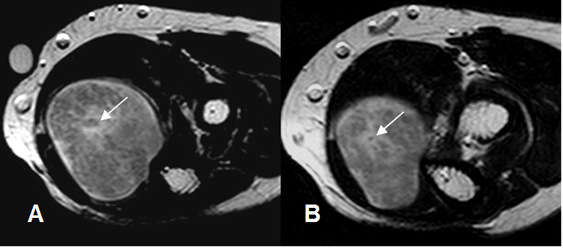

Fig 177. Signo de Target.

A y B: RM axial en T2. Neurofibromas en el nervio ulnar, con signo de Target. (Zona hipointensa central).